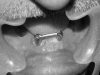

Fig. 6

Dolder bar connecting implants in the region of 33 and 43